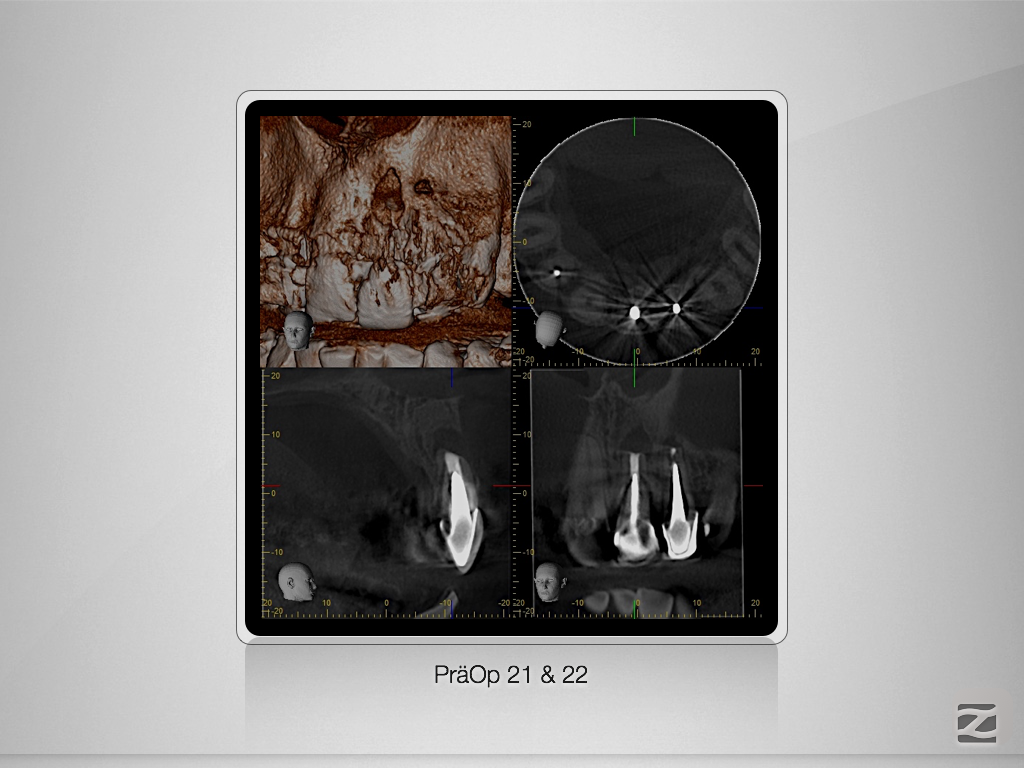

21 22 D.002

Rasche Heilung